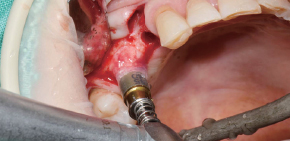

A Clinical Case using Ø3.5/4.0 Harvesting Drill

by Dr. Soohong Kim, DDS, Ph.D

-

Drilling at 300 rpm with irrigation was carried out after marking implant and harvesting position.

The Silicone Shield was brought into close contact with various types of bone level and prevented bone chip loss.

The amount of bone taken was easily ascertained, through the transparent Silicone Shield.

The bone was transferred to bone dish after disassembling the Silicone Shield and Stopper.

The amount of the bone was much more than expected.

After the implant placement, healing abutments were connected and carried out GBR in the defected area.

* 2 Step Harvesting : Drilling to 7mm is recommended after transferring bone chips to bowl since the Stopper & Silicone Shield are fully filled with bone chips while 4mm drilling.